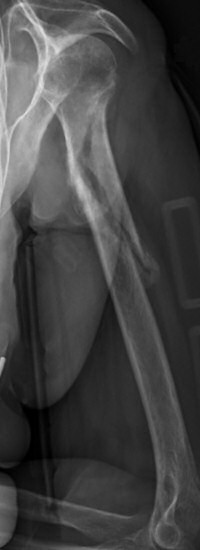

Exempel på humerusfraktur som behandlats icke-kirurgiskt, röntgenbilder efter 19, 40 resp. 71 dagar